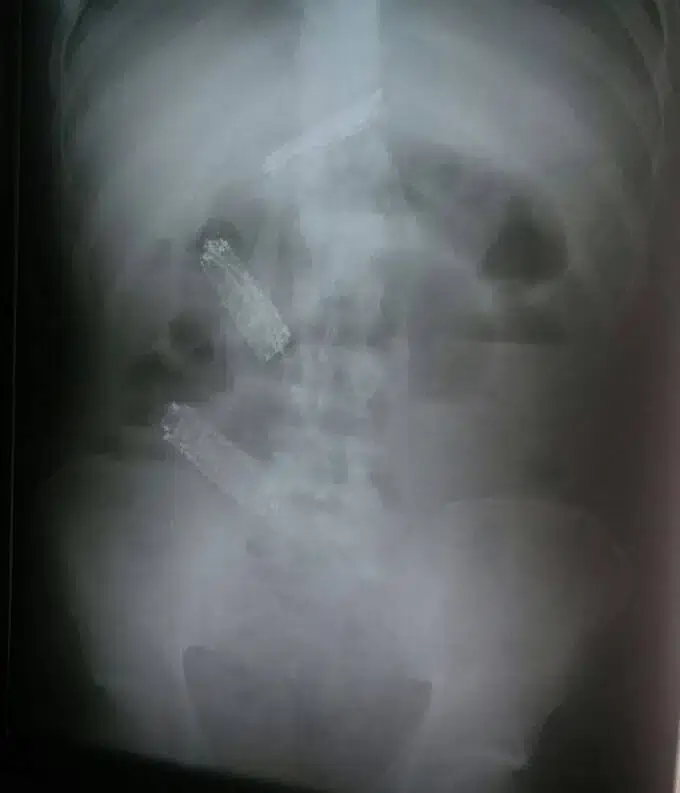

Em um exame raio-X é possível ver os aparelhos em seu estômago. Ele foi medicado com laxantes e voltou à cadeia, mas não conseguiu expelir. Ao retornar ao hospital para fazer uma cirurgia de retirada, passou mal e acabou morrendo.